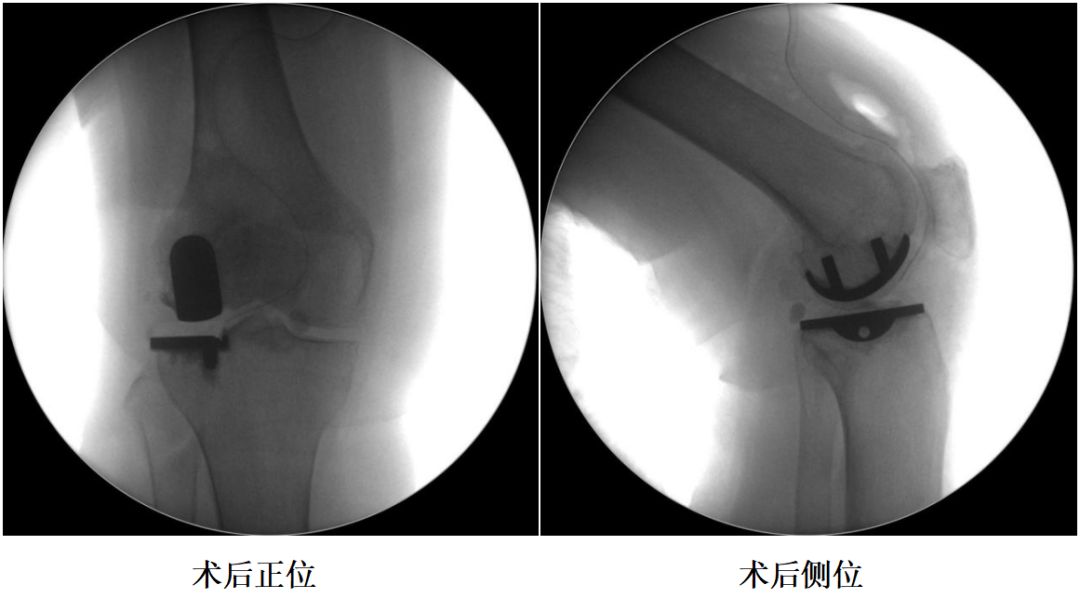

四、术后X透视片

膝关节屈曲45°, 前拉、 外旋胫骨, 安装胫骨假体,假体间插入2mm插片直至骨水泥凝固。

技术要点11:伸直位确定胫骨假体厚度

假体试模复位后屈曲间隙(11mm)>伸直间隙(9mm),在膝关节完全伸展时确定胫骨假体的厚度(9mm) 。